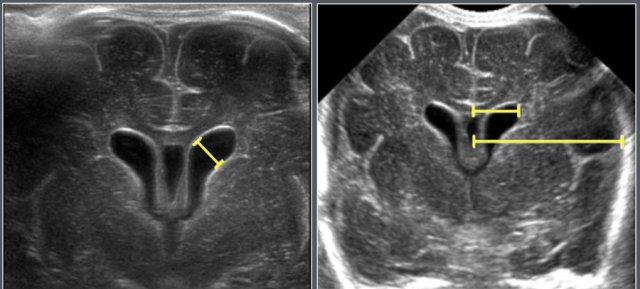

Subarachnoid space

Adapted from reference 5 Adapted from reference 5

The subarachnoid space was assessed using ultrasonography in 278 full-term healthy Chinese infants. Measurements were taken in the coronal plane at the level of the foramen of Monro (figures)

The mean values in the table were calculated from the equations given in the article, the 95% confidence levels were derived from the graphs in the article.

Ultrasonographic coronal representation of the subarchnoid space at the level of the foramen of Monro.

• SCW = Sino Cortical Width

• CCW = Cranio Cortical Width

• IHW = Inter Hemispherical Width.

Causes of enlargement of the subarachnoid spaces:

• BESSI (benign enlargement of subarachnoid space of infancy)

• Brain atrophy

• Dural sinus thrombosis

Ventricles

Adapted from reference 4 Adapted from reference 4

Adapted from an ultrasonographic study of 1483 neonates, gestational age range 25-42 weeks.

The neonates were examinded at day 3.

All neonates with perinatal asphyxia, infection of the central nervous system, intracranial hemorrhages of craniospinal malformation were excluded.

Causes of ventriculomegaly:

• Congenital (e.g. holoprosencephaly)

• Obstructive hydrocephalus

• Communicating hydrocephalus

• Atrophy

The anterior horn width and the ventriculo-hemspheric ratio is measured on the coronal view at the level of the foramen of Monro.